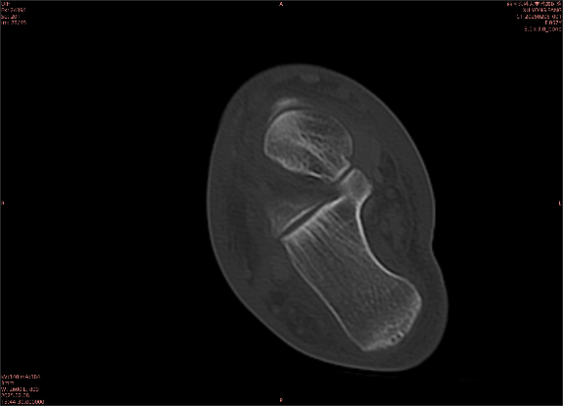

舉例圖像

圖2

專業(yè)解釋看不懂沒關(guān)系,大家看圖1和圖2就可以了,這是同一個(gè)患者跟骨的磁共振和CT圖像,圖1的紅色箭頭指示的黑線就是磁共振圖像顯示的骨折線,一目了然。而對比圖2的CT圖像上并未顯示異常。